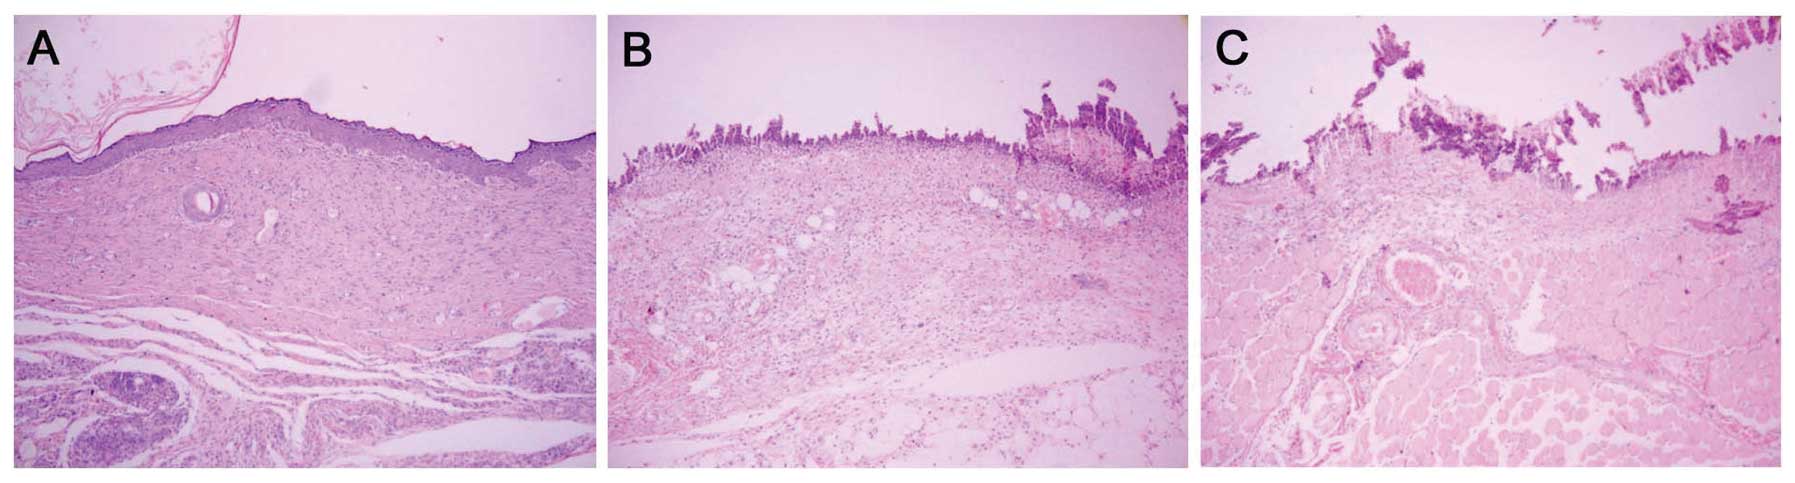

Histological observation demonstrated that on day 4 after infection, the wounds treated with MAMP had no sign of infection and collagen fiber was mature and well arranged, with presentation of intact structure. In addition, regenerative folliculus and sebaceous glands were detected in the fibrous connective tissues (Fig. 4A). In contrast, the untreated group and the placebo group lost nearly all of their epidermis, and the dermis was infected to a certain extent (Fig. 4B and C).

Figure 4

Histological morphologies of the infected wounds in the different groups (H&E staining; magnification, ×100). (A) Intact epidermis, mature collagen fibers and regenerative folliculus and sebaceous glands were detected without signs of infection in the MAMP group. (B) The epidermis was nearly destroyed with necrotic tissue and disorderly arranged collagen fibers in the placebo group. (C) The wound section showed obvious signs of infection, massive necrotic substances and a thin granulation tissue layer without regenerative skin appendages in the untreated group. H&E, hematoxylin and eosin.